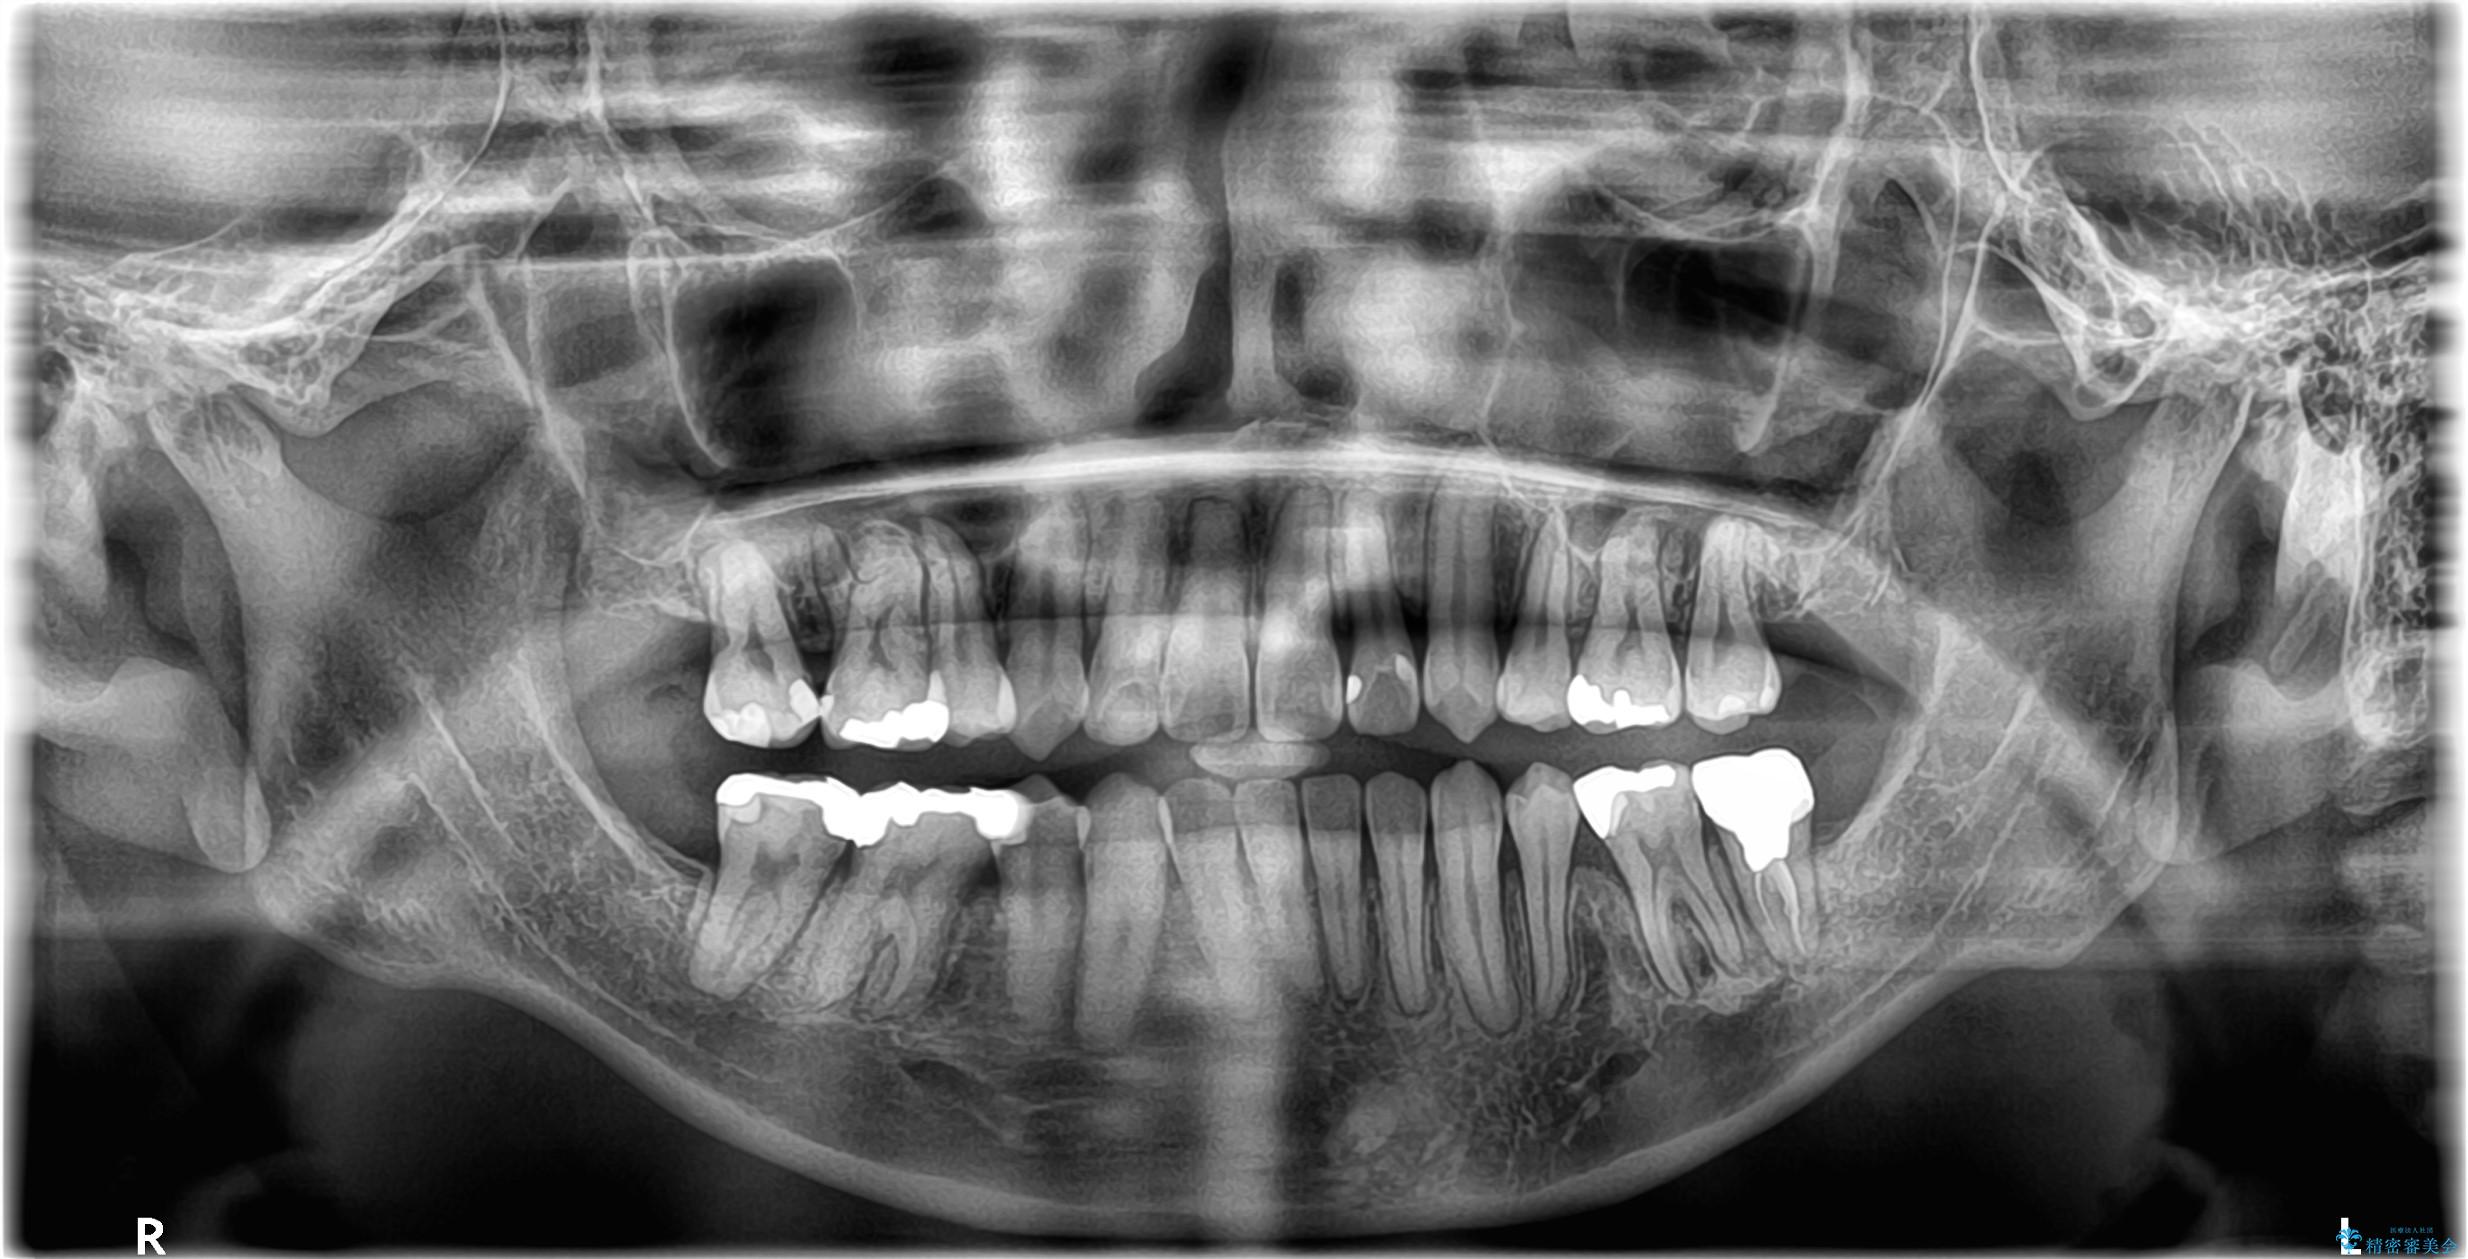

- 開咬と歯のデコボコ(叢生)、八重歯を主訴にご来院された患者様です。

矯正の精密検査の結果、上顎左右4番および下顎左右5番の計4本を抜歯し、ワイヤー矯正(クリア装置)にて治療を行いました。

虫歯があったので、虫歯治療は矯正前に行っています。